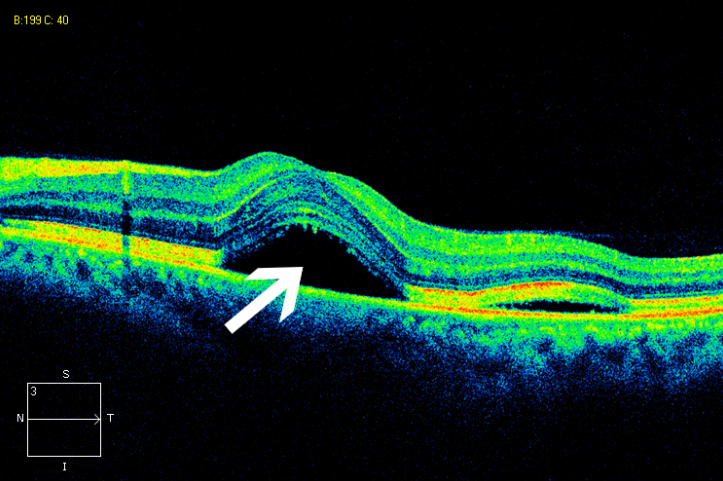

4 中心性浆液性视网膜脉络膜病变

特点:多发于青壮年男性,症状包括眼前暗点、视物变形等。

治疗:PDT、微脉冲激光治疗可缩短病程,避免视力损害。